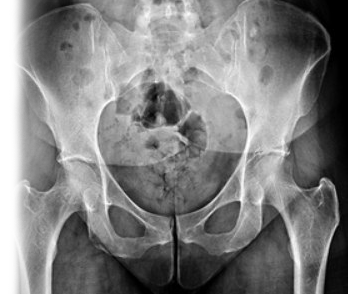

Рентгенография костей таза – важный метод прицельного исследования, который позволяет оценить состояние костей таза.

Диагностическая услуга выполняется в прямой проекции.

Рентген позволяет оценить наличие костно-травматической, дегенеративно-дистрофической патологии костей таза.